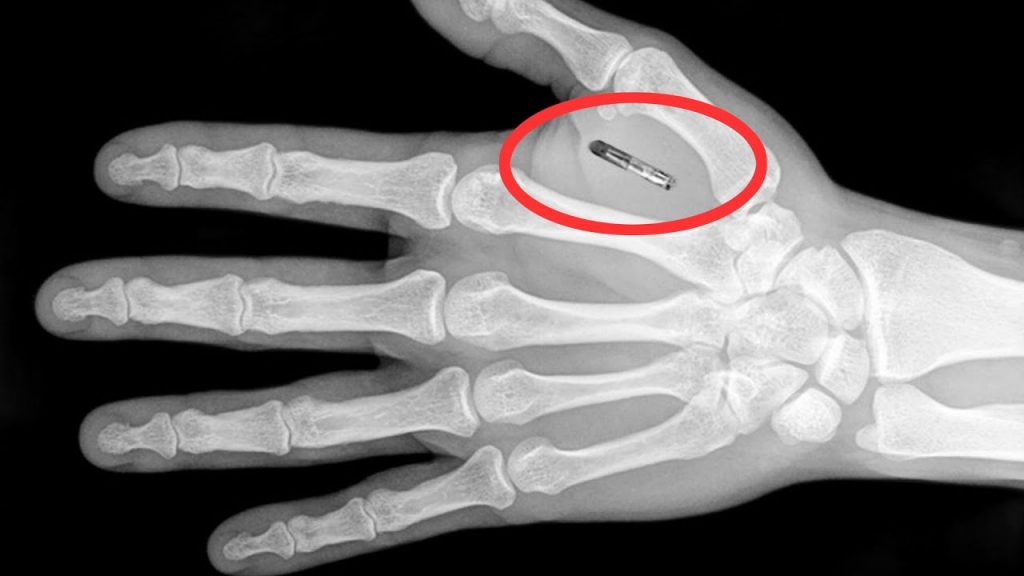

Pero eso no es todo, pues Ben Workman también lleva implantada una llave Tesla en su mano derecha, la que le permite controlar el acceso a su automóvil. Por otro lado, en su extremidad izquierda tiene un imán, chips RFID y NFC que reemplazan parte de la funcionalidad que posee su teléfono inteligente.

Este procedimiento es conocido como biohacking y es muy similar a que se realiza cuando se le colocan microchips a las mascotas. Aunque el momento de colocar este pequeño aparato puede ser muy doloroso, toda esta molestia se va pasando una vez transcurrido el tiempo.

Pero según lo comentado por este "Tony Stark" de la vida real, implantar la llave Tesla fue más complejo. Para esto, el hombre tuvo que hacerse una incisión de casi cinco milímetros en el dorso de su mano, aunque el dispositivo tuvo que pasar un procedimiento especial previo a este momento. "Toman la llave, la disuelven en acetato, la reforman y luego le ponen un polímero médico", comenta Ben Workman, explicando así los detalles que se deben realizar con anterioridad.